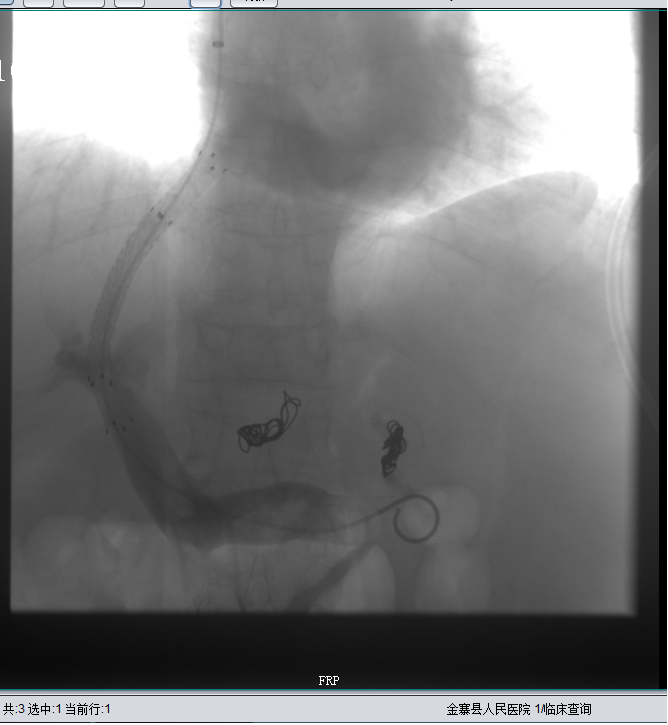

经肝静脉穿刺进入门静脉并显示门静脉

经肝静脉穿刺进入门静脉,建立分流道并显示增粗的胃冠状静脉

胃冠状静脉栓塞后,未见血流

扩张肝静脉门静脉分流道

肝静脉门静脉分流道通畅

2020年1月7日再次出现腹胀伴下肢浮肿等症,至我院外周介入科就诊。上腹部增强CT示:1、肝硬化;2、腹水;3、门静脉高压;4、食管下段静脉曲张;5、脾脏增大;6、脾脏局限性梗死。入院时腹围约51cm,积极完善相关辅助检查,于1月10日行“经颈内静脉肝内门体分流术+胃冠状静脉栓塞术”,术后患者腹胀症状明显好转,腹围约38cm,术后给予保肝、抗凝等对症治疗。